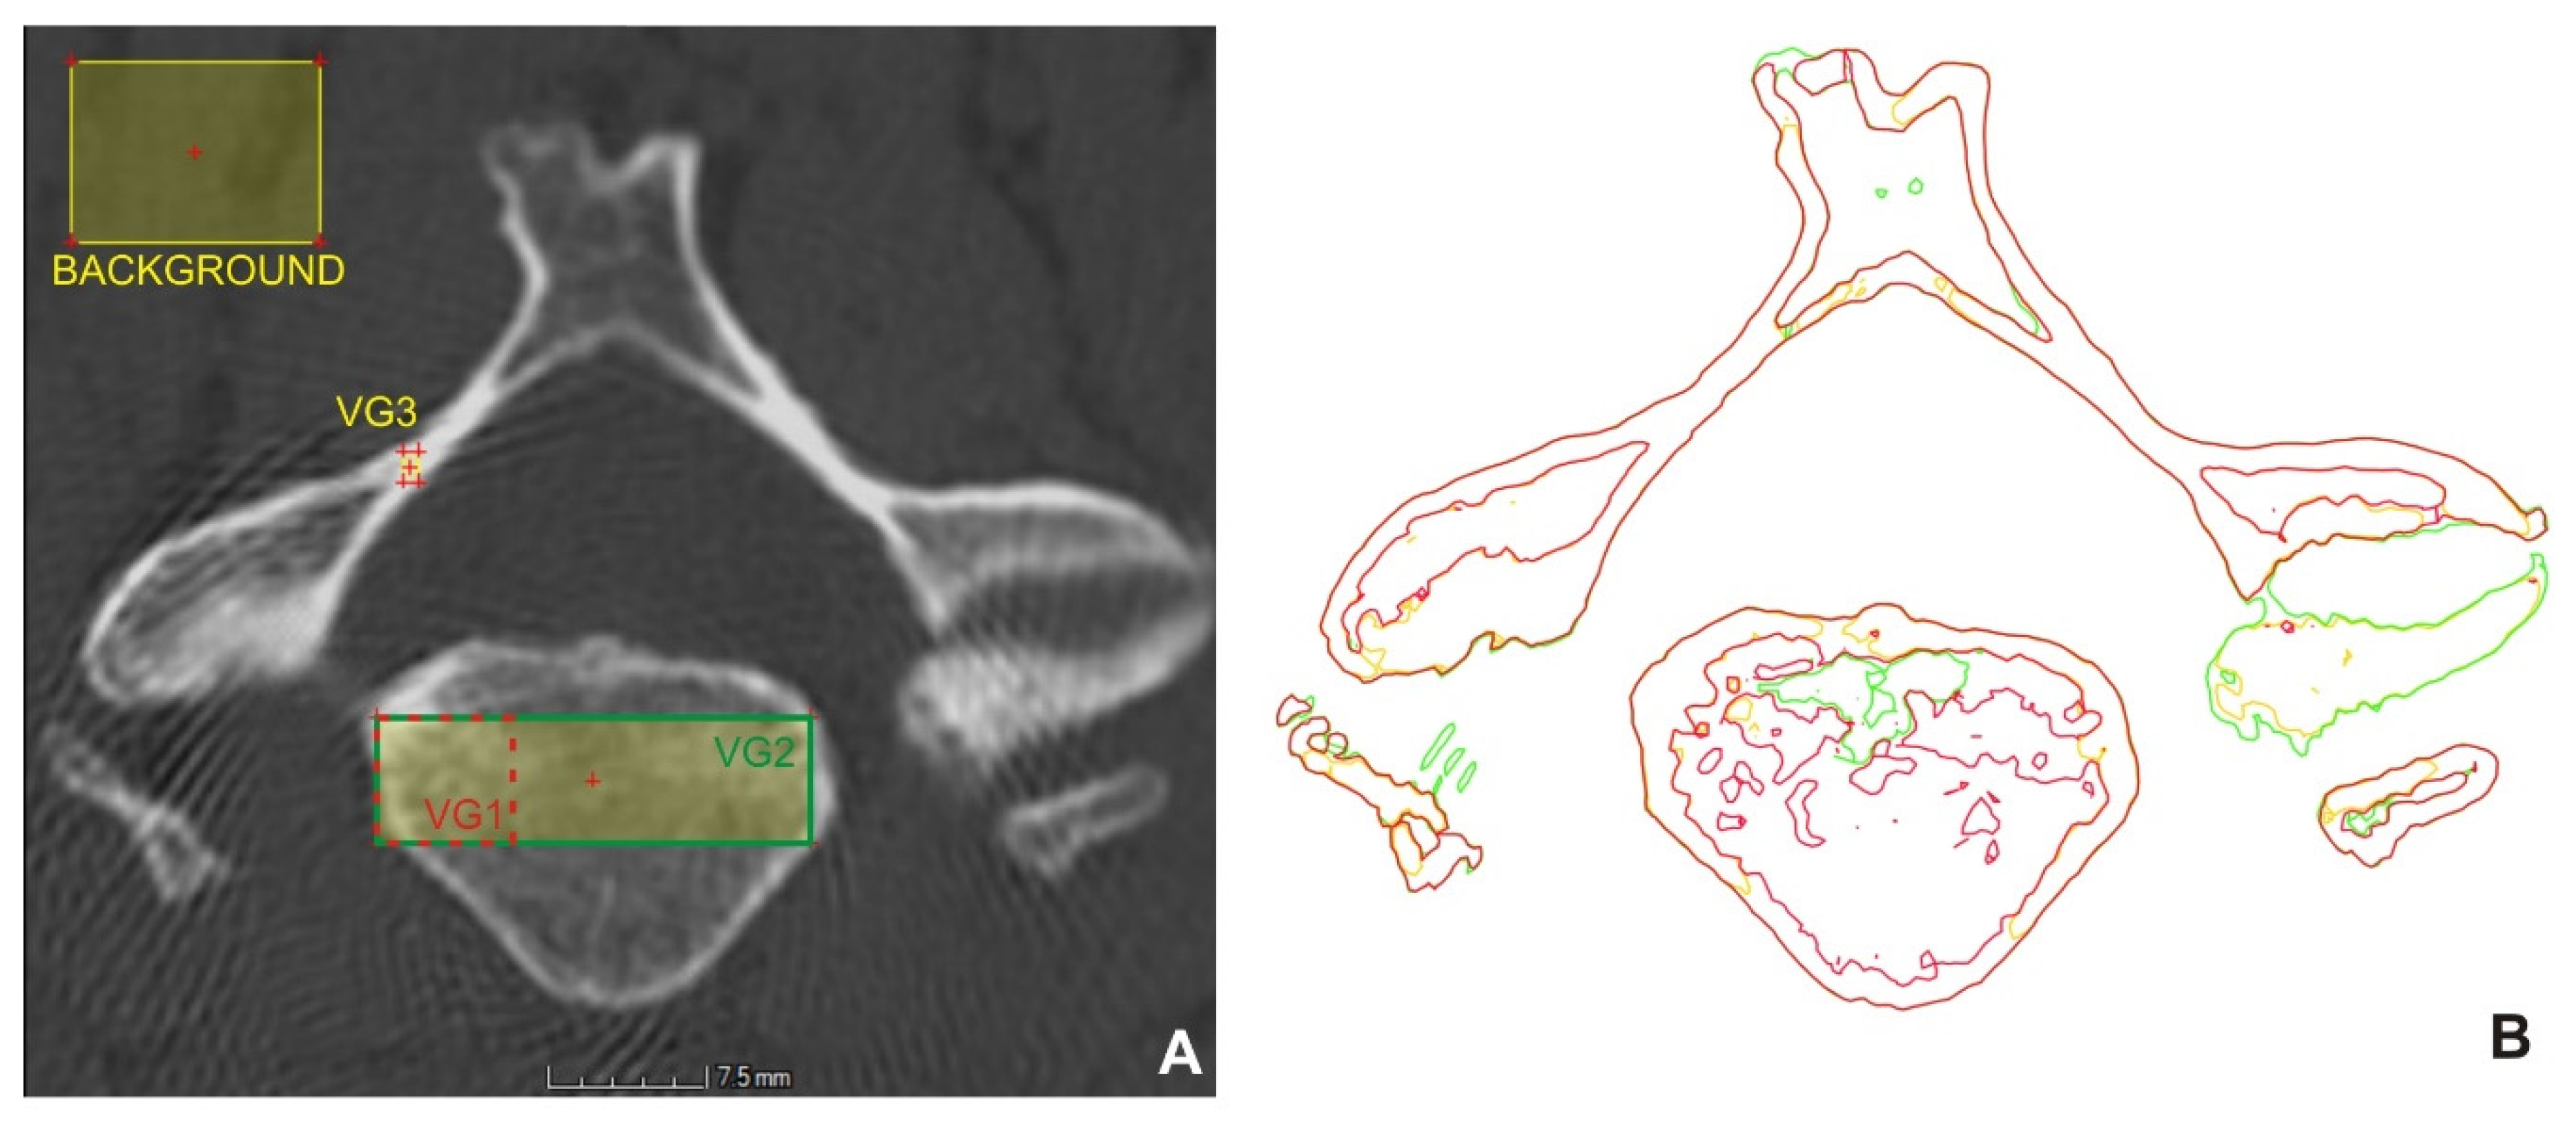

| Surface Determination | VG1 | VG2 | VG3 |

|---|---|---|---|

| Background | 32 | 18 | 29 |

| Material | 743 | 545 | 1746 |

| Isosurface | 388 | 282 | 887 |